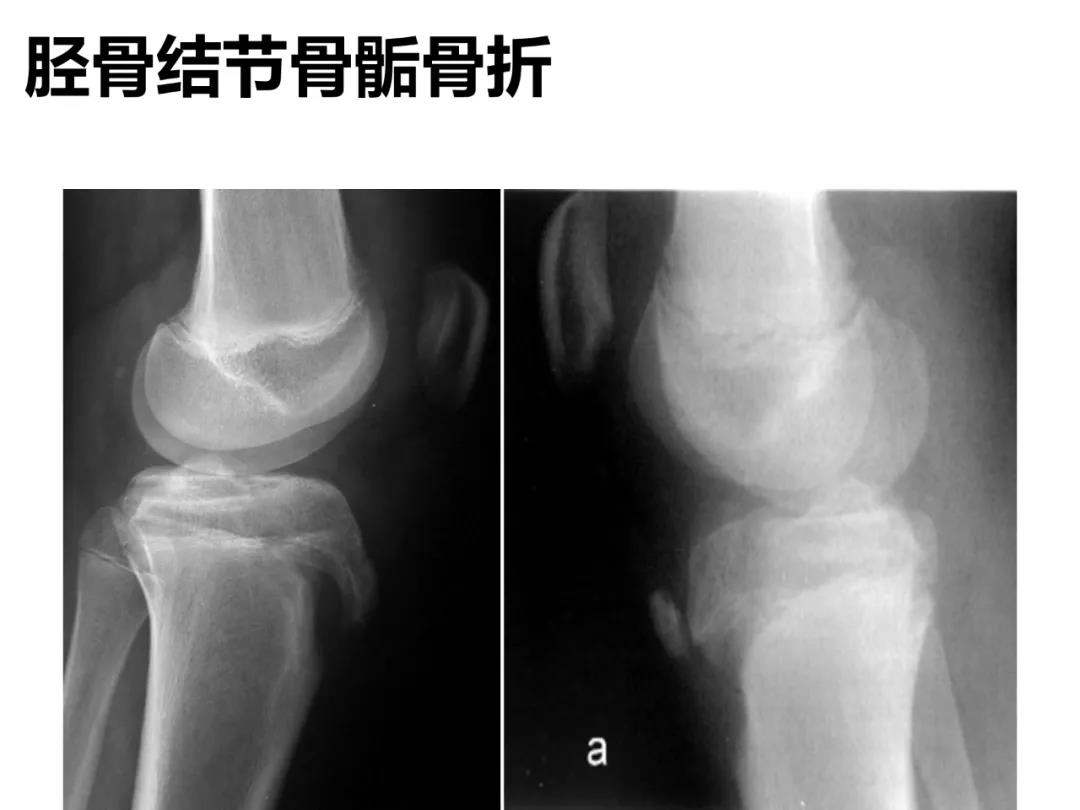

小儿骨科X线片汇总,临床读片宝典!